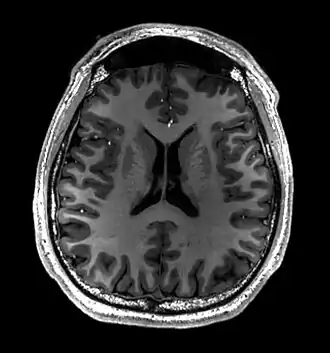

Brain regions on T1 MRI -

T1 (note CSF is dark) with contrast (arrow pointing to meningioma of the falx) -

Normal axial T2-weighted MR image of the brain -